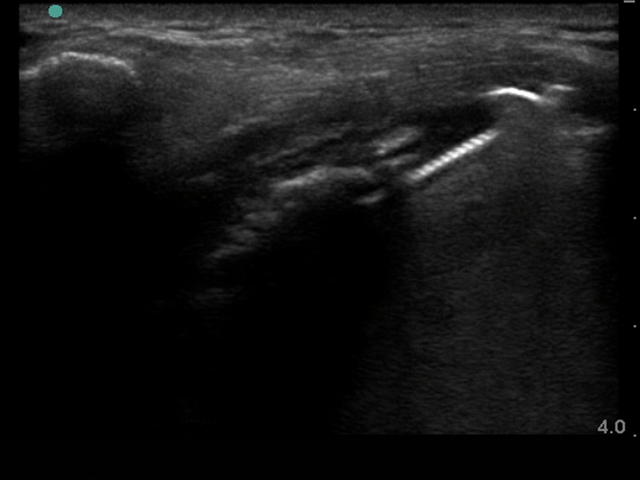

Image - Épaule : Fixation du trochiter, Post-opération